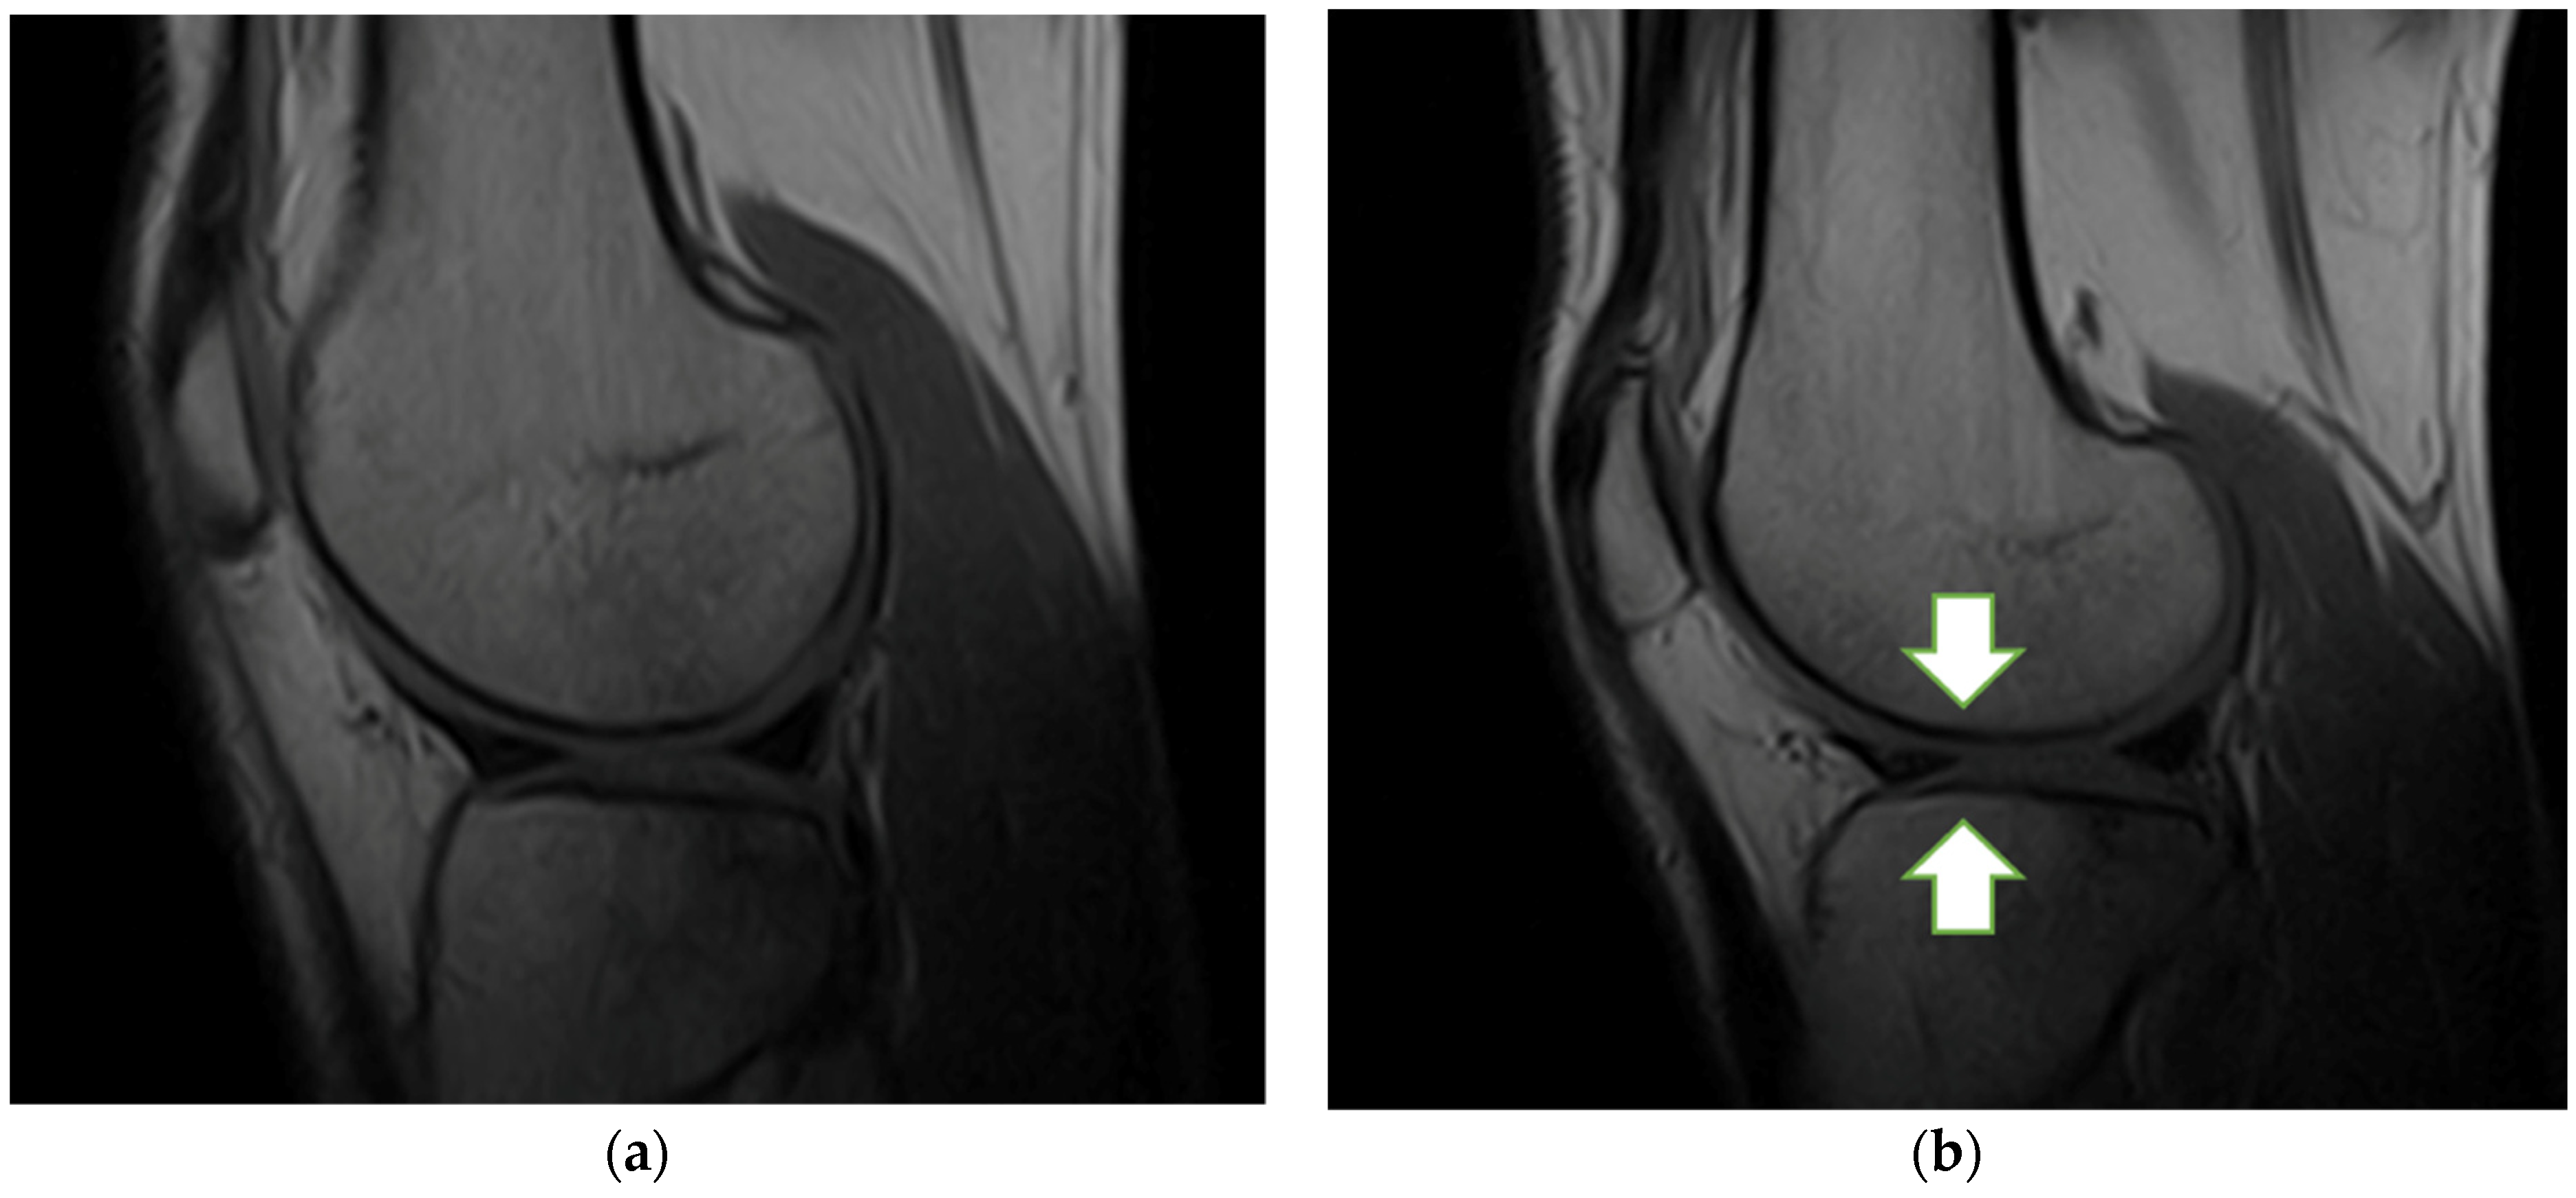

3.5. MRI